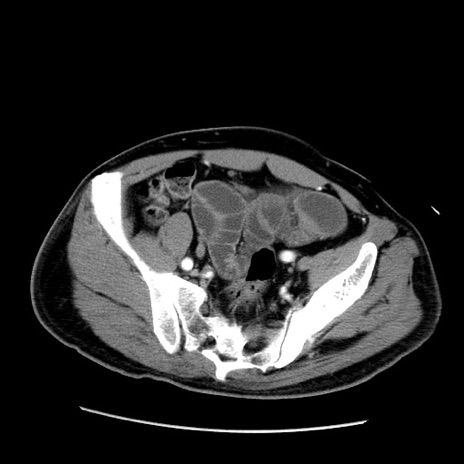

症例22(横断像)

【症例】50歳代男性

【主訴】腹痛

【現病歴】AVMからの被殻出血のため回復期リハ病棟入院中。 本日午後3時頃急に下腹部痛が出現した。

【既往歴】AVM、被殻出血、虫垂炎、高血圧

【身体所見】意識晴明、左半身不全麻痺、会話の理解は良好、36.5°C、腹部:膨隆、全体に板状硬、下腹部正中に圧痛点あり、反跳痛-、筋性防御不明、右下腹部にope scar

【データ】WBC 9400、CRP 0.06